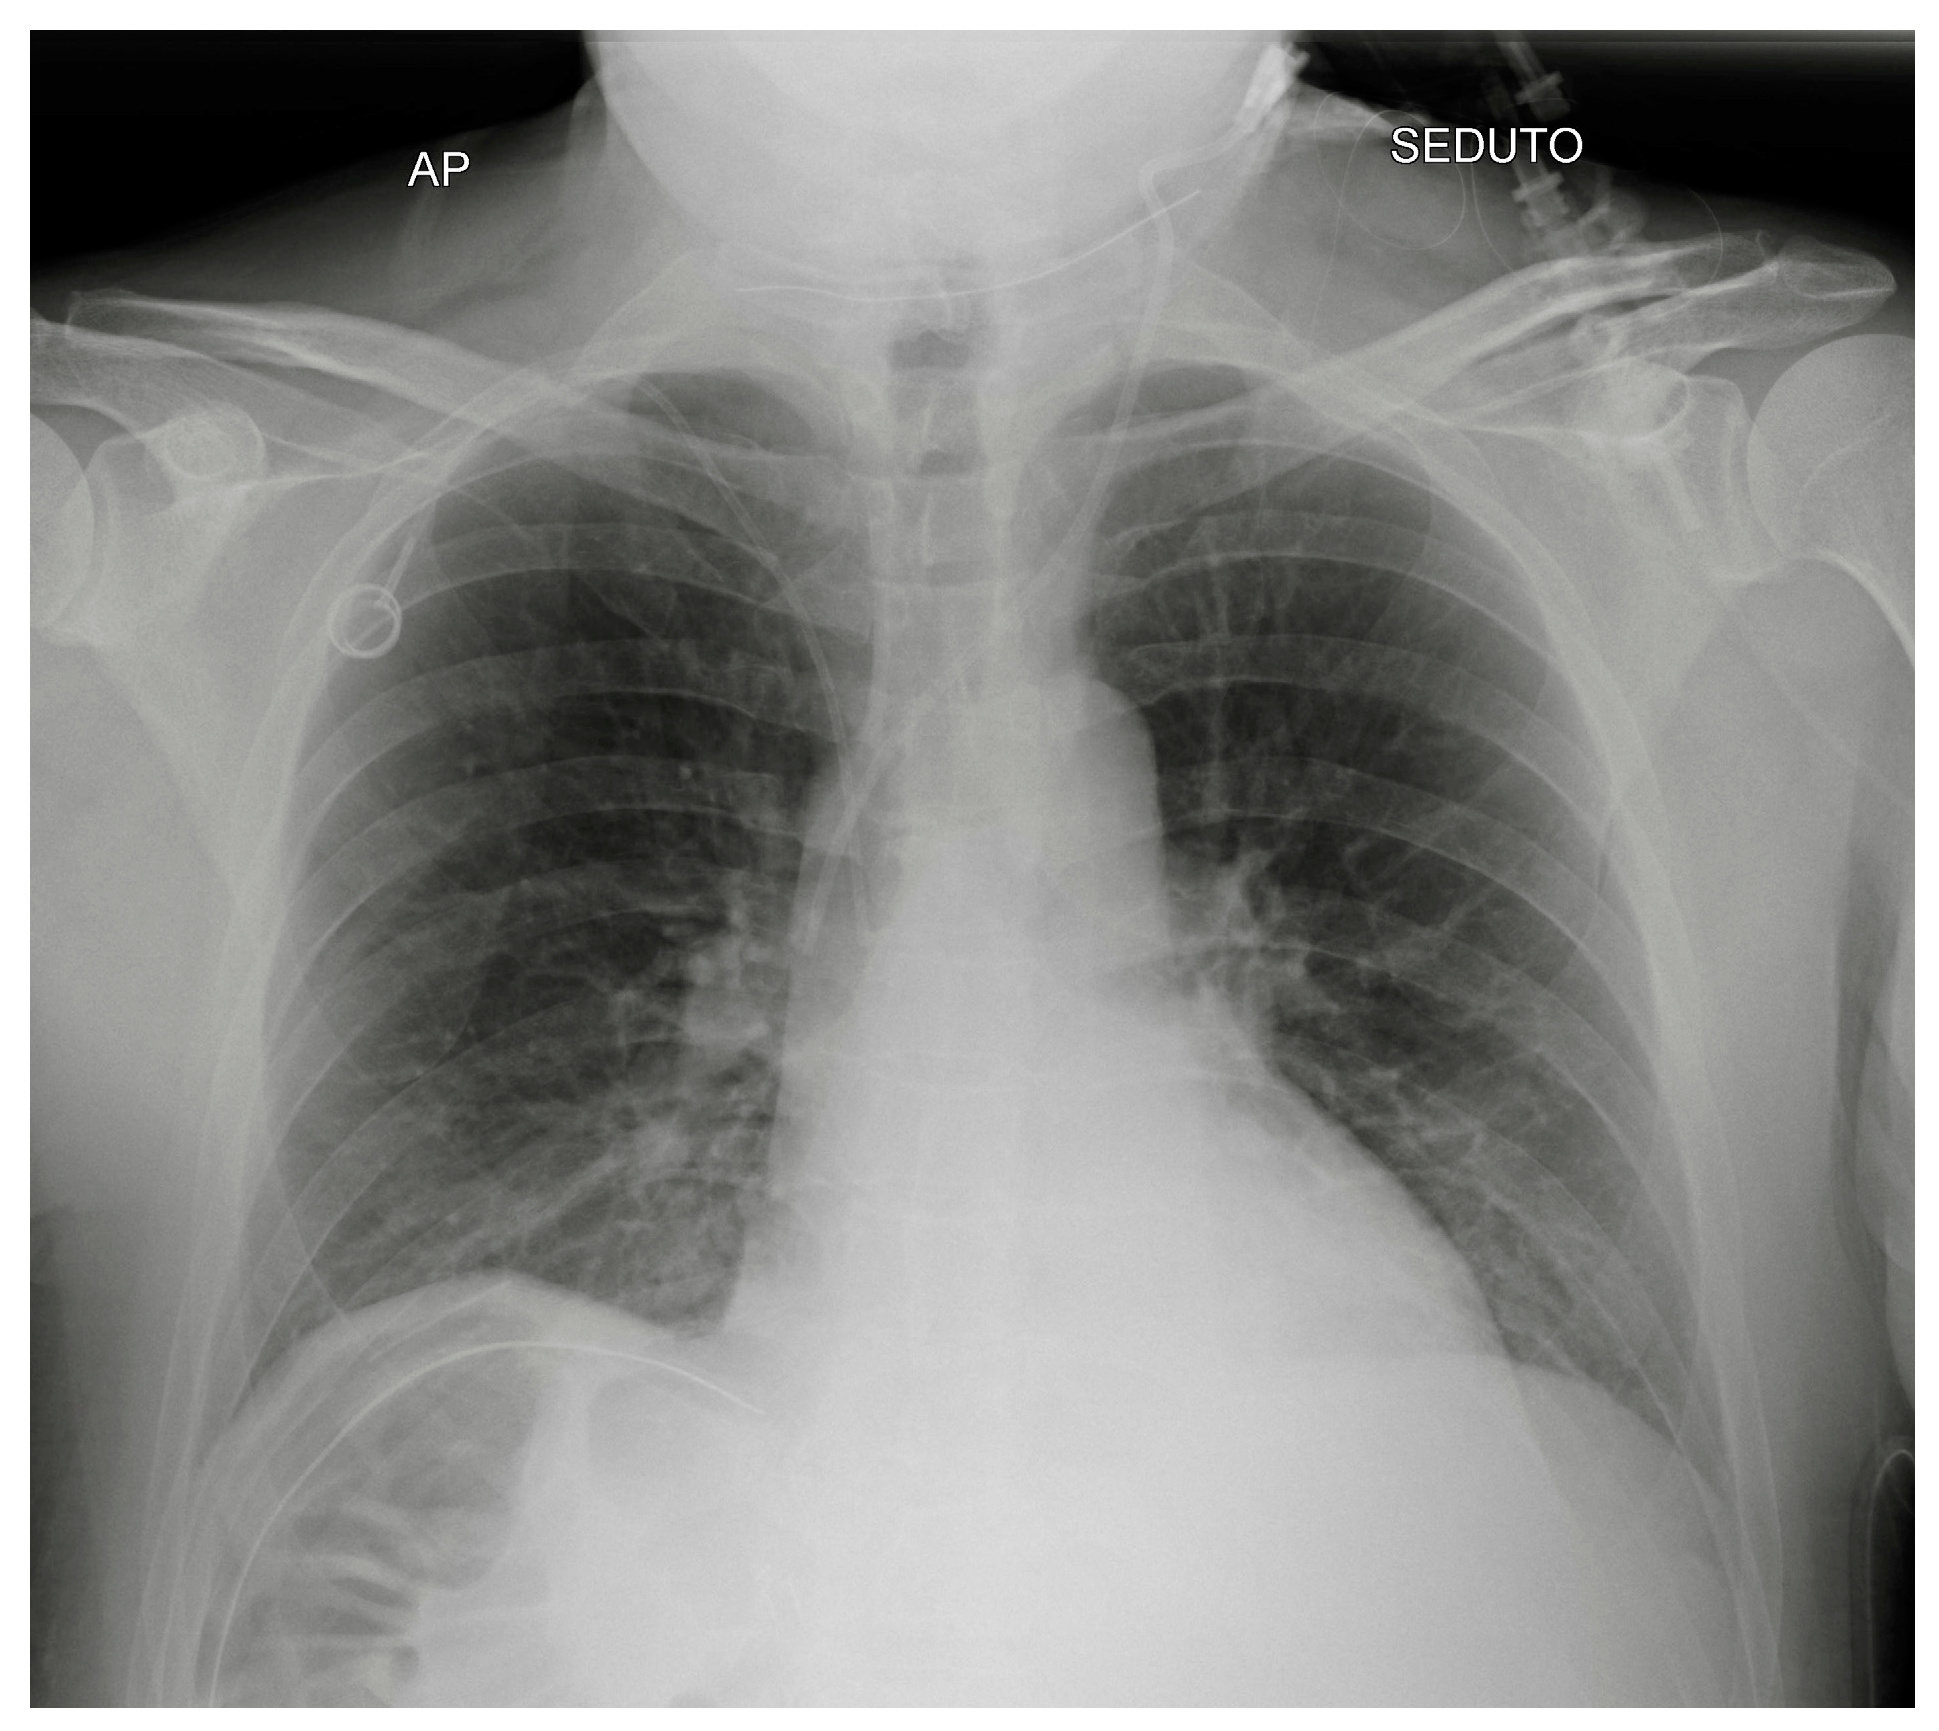

Potential confounding factors are EKGs’ leads, external tubes, artifacts and overlapping of different devices. The need to have at least two orthogonal projections to correctly locate a device can be a limit in patients in which only an anteroposterior projection is feasible. Moreover, technical factors must be considered, such as the orientation of the X-ray tube and patient rotation (Figure 1) [2].

Figure 1.

Potential confounding factors when checking for devices on a CXR. (a) Anteroposterior CXR of a right-sided rotated patient can simulate the dislocation of the central venous catheter (white arrows). (b) Anteroposterior CXR of a patient with multiple devices and external EKG leads.